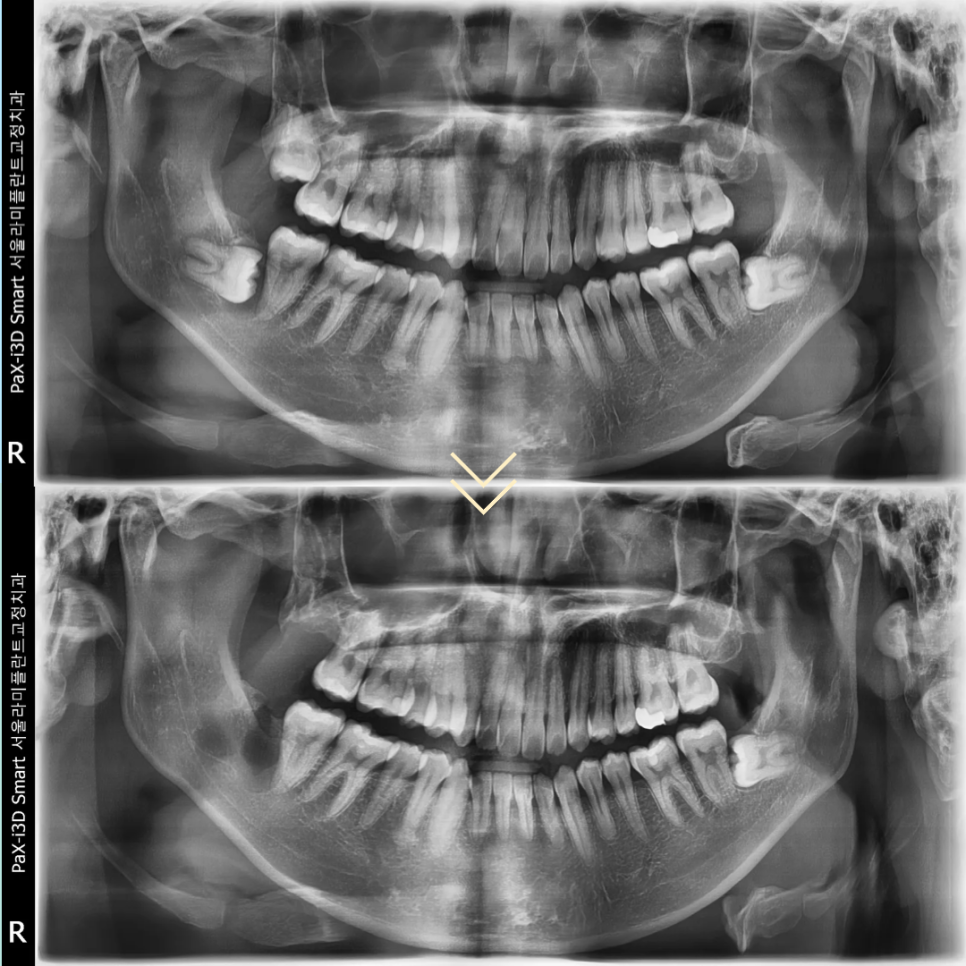

대학병원에서도 전신마취가 필요하다고

판단할 정도의 어려운 케이스였지만

동탄역치과는 당일 내원 후 국소마취만으로

발치와 낭종 제거를 모두 마무리할 수 있었습니다.

발치 다음날 환자분은 소독을 위해 내원하셨는데

수술 부위에 합병증이나 신경 손상 증상은

전혀 관찰되지 않았으며

부종도 크지 않아 일상생활에

바로 복귀하실 수 있었습니다.